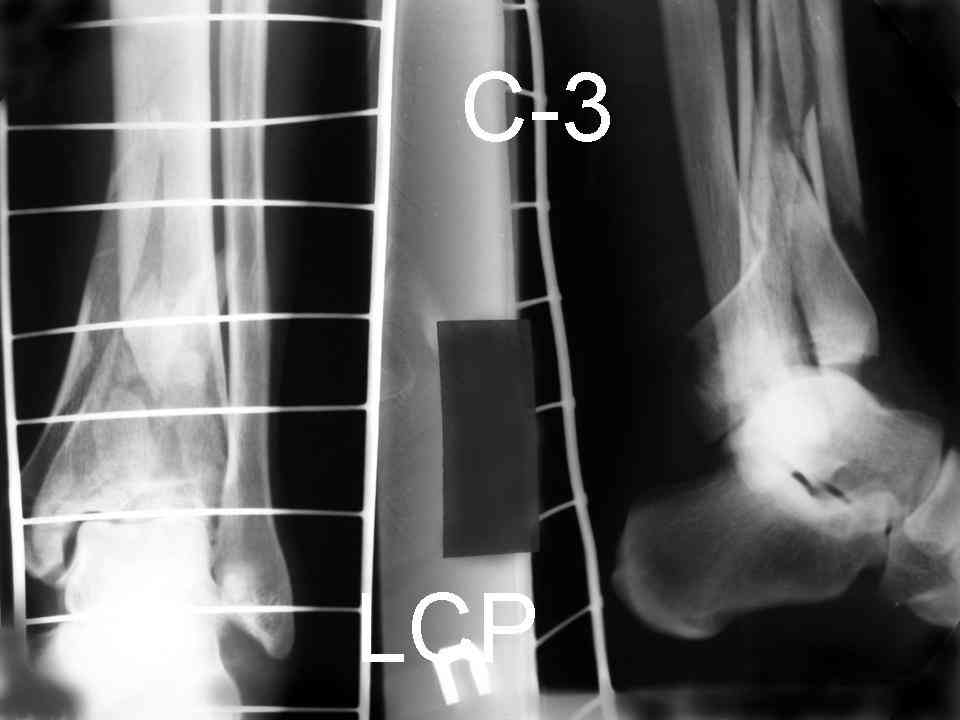

На рентгенограммах типичный перелом пилона по типу С-3. есть опыт до 100 открытых опреаций у нас в клинике. 20 примерно в год. Принцип один -все внутрисуставные переломы нуждаются в открытой репозиции и внутренней стабильной фиксации. При поступлении КТ не надо, так как получается только нагромождение костей. Истинной картины нет. Главное восстановить длину малоберцовой кости - это ключ к успеху. При поступлении меньше всего надо думать о сосудистых расстройствах, т.к. сама операция и репозиция даже сначала частичная даёт улучшение сосудитых нарушений. Причём очень быстро. Операция в 2этапа. При поступлении доступ позади наружной лодыжки, причём обязательно. После этого репозиция малоберцовой кости и фиксация пластиной 1/3 трубки под винт 3,5. Дренаж и любой аппарат наружной фиксации. Затем после спадения отёка на 5-7-10 день аппрат снимается и дугообразный разрез спереди от медиальной лодыжки 10-12 см. Главной чтобы расстояние между 1 и вторым разрезом было не меньше 7-8 см. Тогда не будет некрозов лоскутов. Таранная кость используется как матрица на неё укладываются отломки и фиксируются пицами. Ренг-контроль. Отломки лежат все отдельно, но ничего не высыпется. При переломах С-3 всегда нужна костная пластика (из крыла). Фиксация пластиной лист клевера простой или LCP. Гипс не нужен. Дренаж до 48 часов. Операция длится 3-4 часа обязательно без жгута. Посылаю примерно такой же случай.

Отправитель: Дрягин В. 04 Январь 2007, 09:00

Послала ещё два снимка, если не пройдут, пошлю ещё. Дрягин. Если есть вопросы, готов ответить.

Посылаю результат лечения предыдущего больного через год.